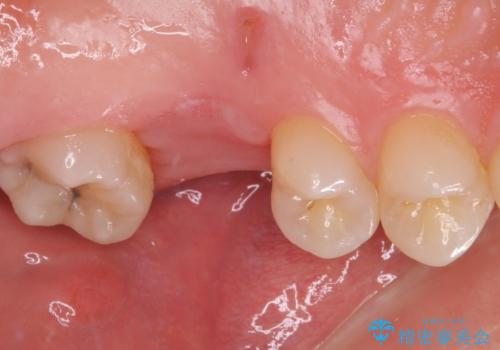

奥歯の虫歯は抜歯が必要であったので、矯正治療前に抜歯をし、矯正治療と並行してインプラントによる補綴治療を行うこととしました。